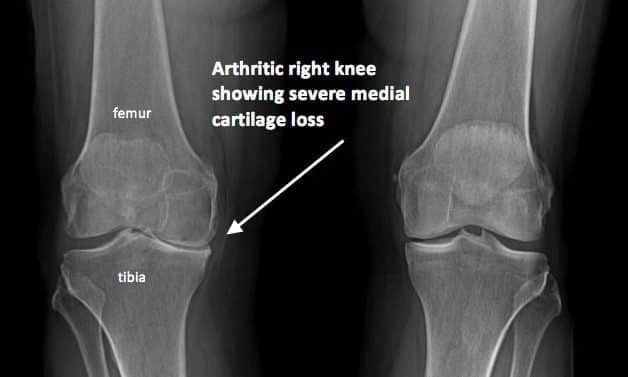

Tahap paling parah. Dari gambaran xray. tulang peha dan tulang betis sudah bertemu antara satu sama lain. Tulang rawan sudah tiada lagi. Pada keadaan ini, amat susah untuk berjalan. Sendi menjadi ketat, dan kaki sudah mula membengkok bila berdiri tegak. Kebiasaannya sudah bergantung kepada kerusi roda untuk bergerak. Sudah tidak boleh melipatkan sendi lutut. Pada tahap ini rawatan sakit lutut yang tinggal hanyalah pembedahan menggantikan sendi dan kosnya sangat mahal.